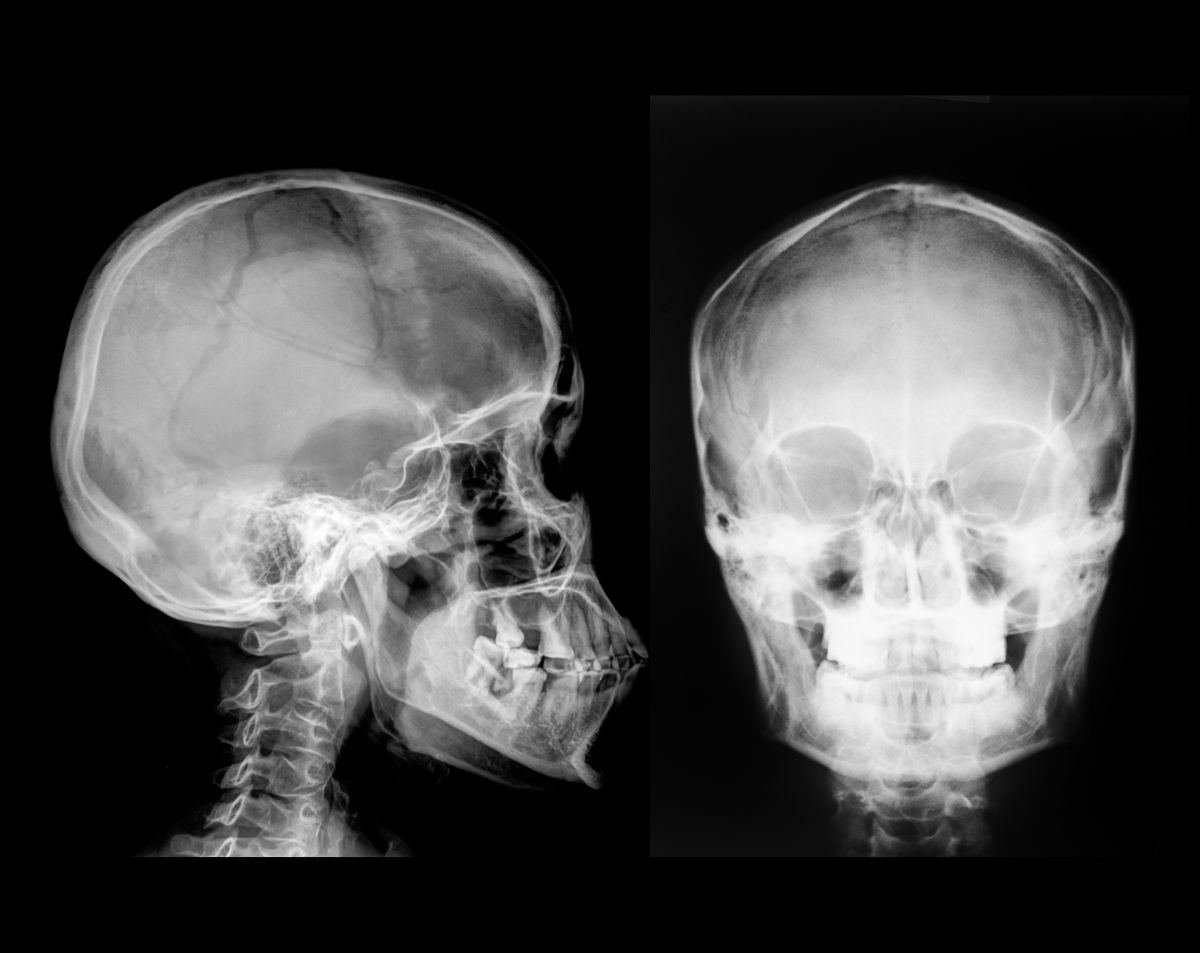

A skull X-ray is a fast and reliable imaging test that produces clear pictures of the bones in your head. Doctors use it to evaluate fractures, detect bone abnormalities, and assess conditions involving the skull, sinuses, or facial bones. Unlike advanced imaging such as CT or MRI, a skull X-ray offers a quick first look, helping providers decide if further testing is needed.

A: Yes. We use modern, low-dose digital X-ray equipment that minimizes radiation exposure while providing precise images.